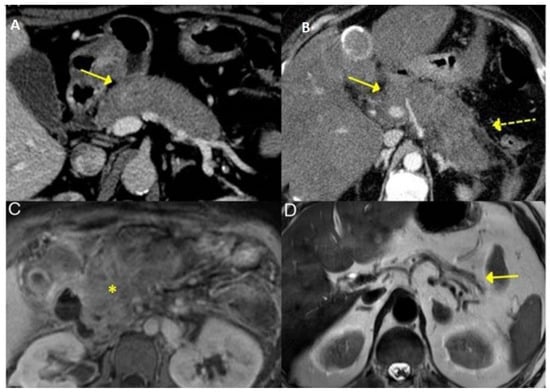

3.2.3. Pancreas

3.2.4. Liver and Bile Ducts

3.2.5. Retroperitoneum